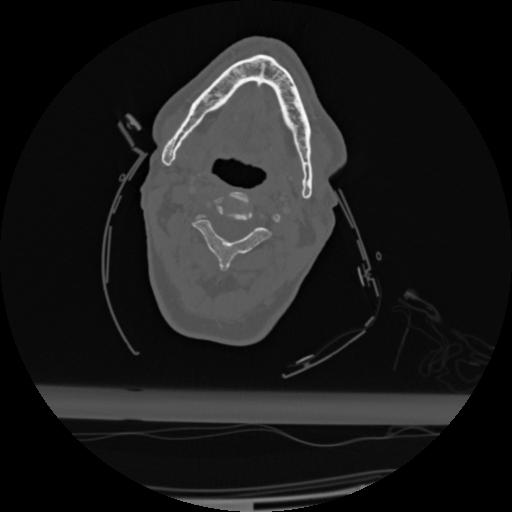

22 ANGIO,CE,Vol,0.5,ANGIO,,